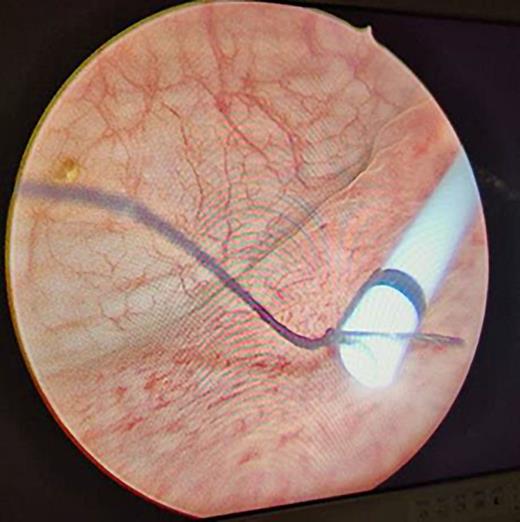

With considerable curiosity, we have read a recent article by Korkes and associates [1]. The article’s focus was on the medical management of stent-related symptoms, specifically the use of alpha antagonists, antimuscarinics, and PDE inhibitors either separately or in combination to lessen the symptoms associated with stents. The distal end of the DJ stent is known to cause pain and voiding symptoms, which is one of the causes contributing to stent-related symptoms [2]. Symptoms can be greatly reduced with a small modification to the ureteral stent. The traditional DJ stent’s lower coil is cut, and its lower end is stitched with a 5-0 mersilk (Fig. 1). Having placed it under fluoroscopy supervision (Fig. 2), we then bring the suture beyond the urethra and sew it to the labia majora in females and the glans penis in males (Fig. 3). We ask the patient to come to the outpatient department on the day of the stent removal. In the office environment itself, we cut the thread and pull the stent together with the thread under all hygienic circumstances. This method can greatly lessen the symptoms associated with the stent while also saving the patient a great deal of money and time. The evidence in favor of our position comes from a trial [3] in which the DJ stent’s distal coil was taken out for a custom-made distal coil that had a 0.3 Fr suture that reached the bladder and shown lower SRS and improved tolerance.